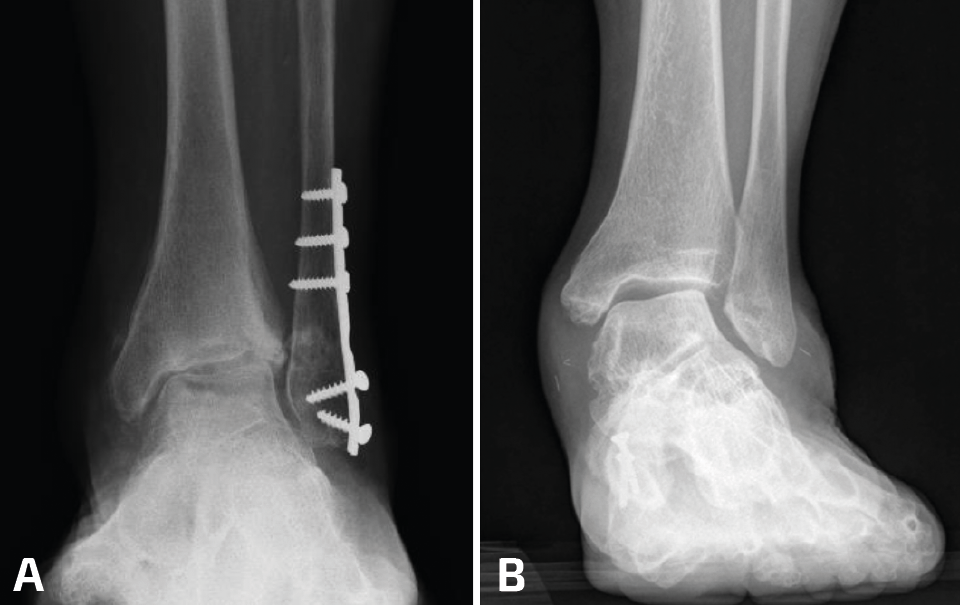

• Traumática: es la causa de hasta el 80% de las artrosis de tobillo en general y también la más frecuente de aquellas en valgo(1,2). En el caso de las artrosis asimétricas traumáticas en valgo la causa más frecuente son aquellas fracturas con compromiso articular con impactación del plafón tibial lateral (Figura 1A).

• Pie plano valgo del adulto (PPVA) (Figura 1B). La deformidad en PPVA es otra causa de artrosis asimétrica importante. No en vano la clasificación de Myerson y Bluman del PPVA tiene un grado específico para este escenario: el PPVA de grado IV(3).

Figura 1.